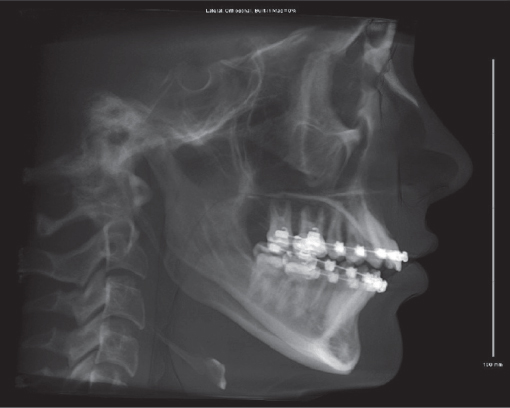

The assessment of craniofacial dimensions is important in diagnosing structural facial dysharmony. Attempts have been made for years by artists, surgeons, and orthodontists to analyze and quantify the proportions of the face. Cephalometry, the scientific measurement of the dimensions of the head, was first used in orthodontics to assess craniofacial growth. Another method for craniofacial analysis based on cephalometry is cephalometric radiography. Although cephalometric radiography was originally introduced into orthodontics during the 1930s, widespread acceptance of the method has only occurred during the past 20 years. 3 In 1931, Hofrath and Broadbent simultaneously and independently developed methods for the production of standardized cephalometric radiographs. 4 This standardization is achieved using a specialized device, known as a cephalostat, which holds the head in a fixed and reproducible position ( Fig. 70.7 ). 5 The cephalostat stabilizes the head with three rods. One rod fits in each external auditory meatus, and a third rod rests passively on the inferior orbital rim or the nasofrontal suture. The radiograph taken is a true lateral view, with no head rotation in the sagittal plane. The cephalometric film should be taken with soft tissue technique to most clearly demonstrate the relationship between the soft tissues and the facial skeleton. 6 To further standardize the radiograph and to minimize distortion, a consistent subject-to-film distance and X-ray target-to-subject distance must be used.

The cephalometric radiograph obtained provides a twodimensional outline of the lateral aspect of the craniofacial skeleton ( Fig. 70.8 ). It can be traced onto a matte acetate sheet to provide a model on which various analyses may be performed. However, this radiograph is subject to image distortion. The acetate model is also subject to tracing error. The purpose of the cephalometric tracing is to provide objective data that assist in the diagnosis and treatment of facial skeletal deformities.

The cephalometric radiograph allows objective evaluation of bony and soft tissue morphology. To effectively use the lateral cephalometric tracing, standardized bony landmark points must be defined. 7 These skeletal landmarks may then be used to derive reference lines and angles ( Tables 70.1–70.3 ).